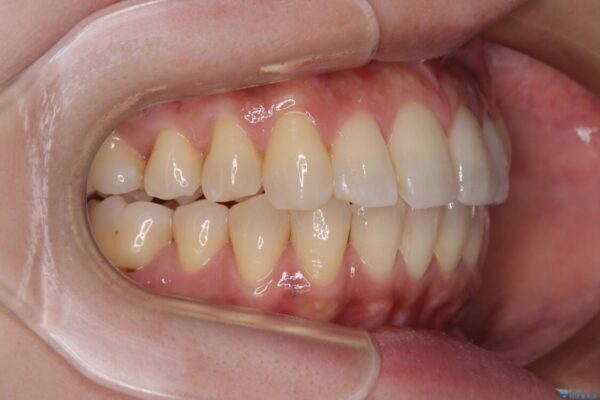

治療後について

歯の傾斜が改善され、インプラントによるクラウンが装着されたことで、物が挟まることもなくなりました。

治療後

• インビザラインによる矯正治療と奥歯のインプラント治療 治療後画像